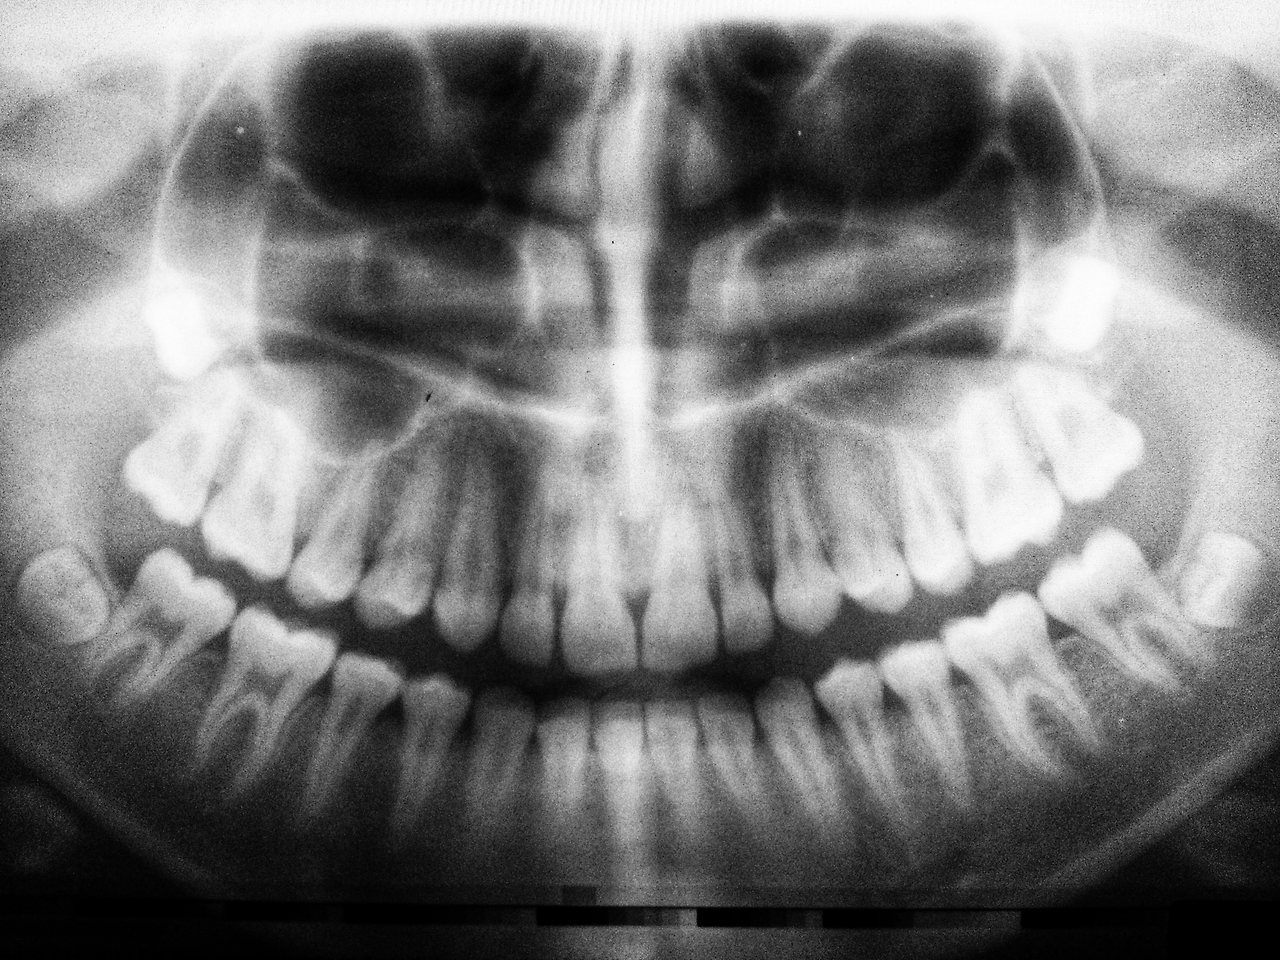

치과에 갔는데 충치가 아니라 사랑니가 부어서 앞에 있는 어금니를 건드린 거 같다고 했다.

사랑니를 뽑는 게 가장 좋은 데 잇몸 안에 감춰져 있어서 뽑는데 좀 어려울 거라 말했다.

이와 이 사이가 깨진 게 맞고,

이가 똑바로 나야 하는데, 지난번에 부었던 사랑니 때문에 기울어져 이가 났기에 음식물이 잘 낄 수밖에 없었다 한다. 그 때문에 이와 이 사이가 충치가 생겼고 이가 깨어져 나간 것이다.

방향 때문에 사랑니를 뽑고 앞에 어금니를 밀어서 충치 치료한 뒤에 다시 당기는 방법이 있지만 이건 이론적인 것일 뿐.

사이에 생긴 충치라 그냥 때우면 떨어질 수 있어 이 가운데 충치와 함께 치료해 끼워주는 형태로 한다고 한다.